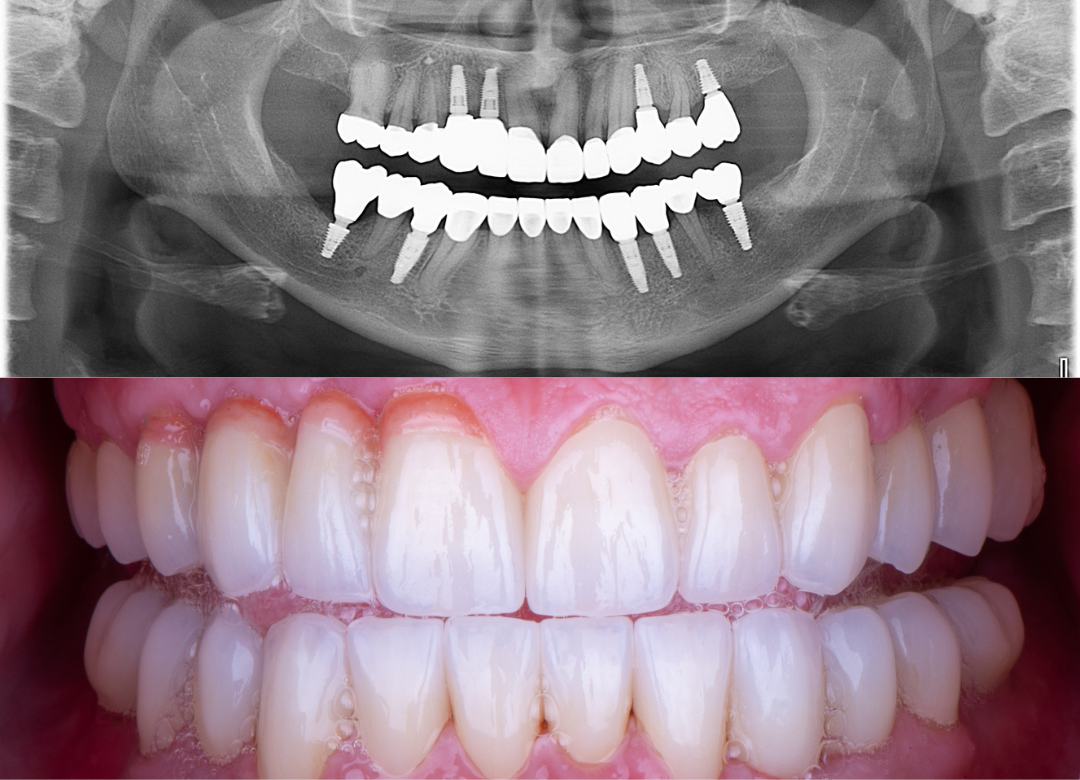

Example transformations achievable with dental implants